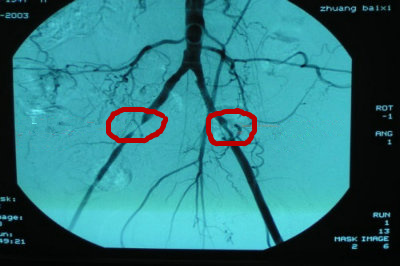

主任介绍:在当前技术条件下静脉血栓是可以完全治疗的,静脉血栓是指在静脉血流迟缓,血液高凝状态及血管内膜损伤条件下,静脉发生急性非化脓性炎症,并继发血栓形成的疾病。绝大多数静脉血栓形成发生在盆腔及下肢的深静脉。多见于产后、骨折及创伤、手术后的病人。